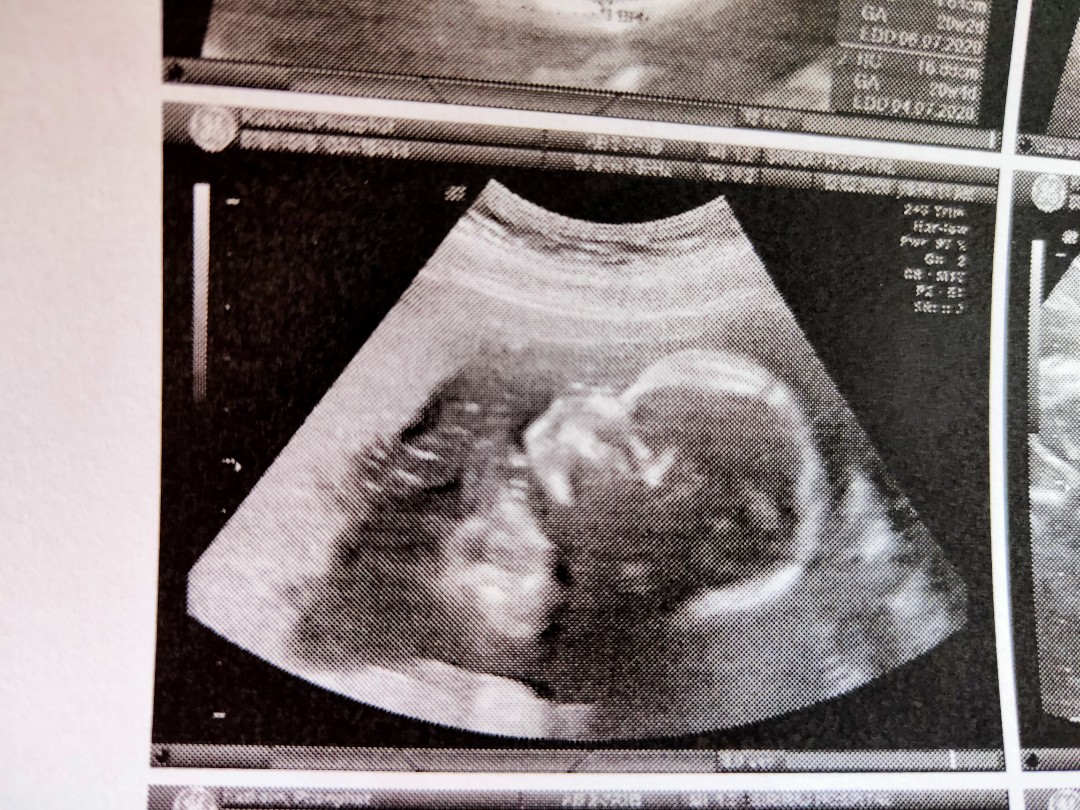

บ้านนี้ ได้ลูกชายค่า กำหนดคลอด 11 ก.ค แม่ๆทีมกรกฎาคมรู้เพศกันยังคะ 19 w 3 d

ลูกชายกำหนดผ่า 2/7/63